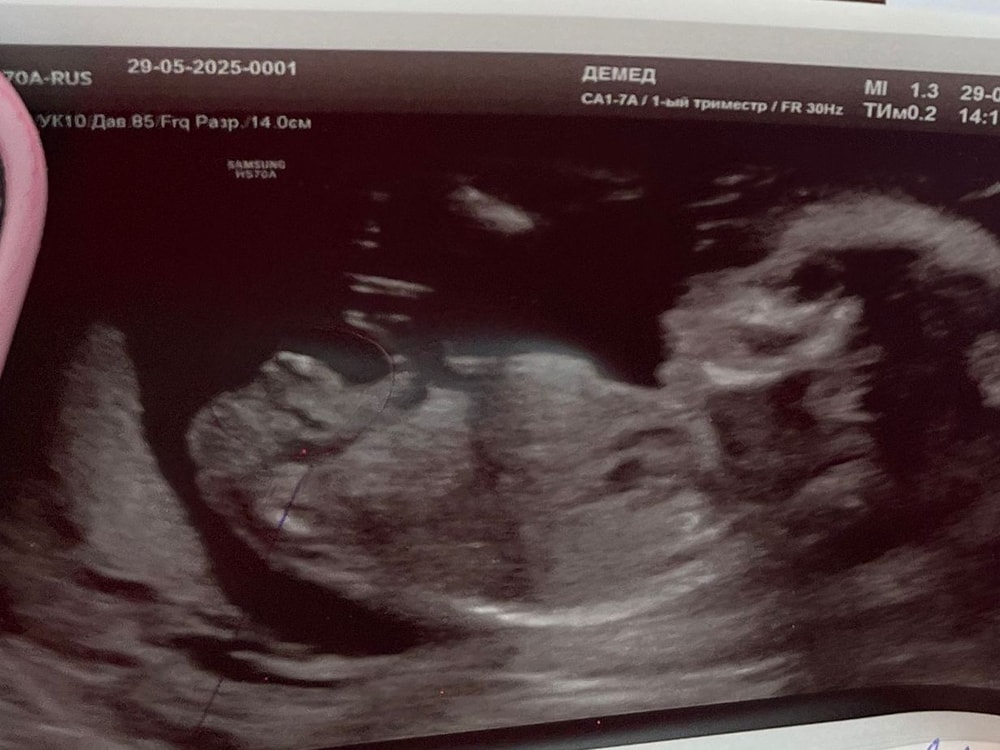

Девочка ?) 17 недель , вчера было гендер пати!😍

УЗИ с уверенностью сразу за девочку написала 🤗